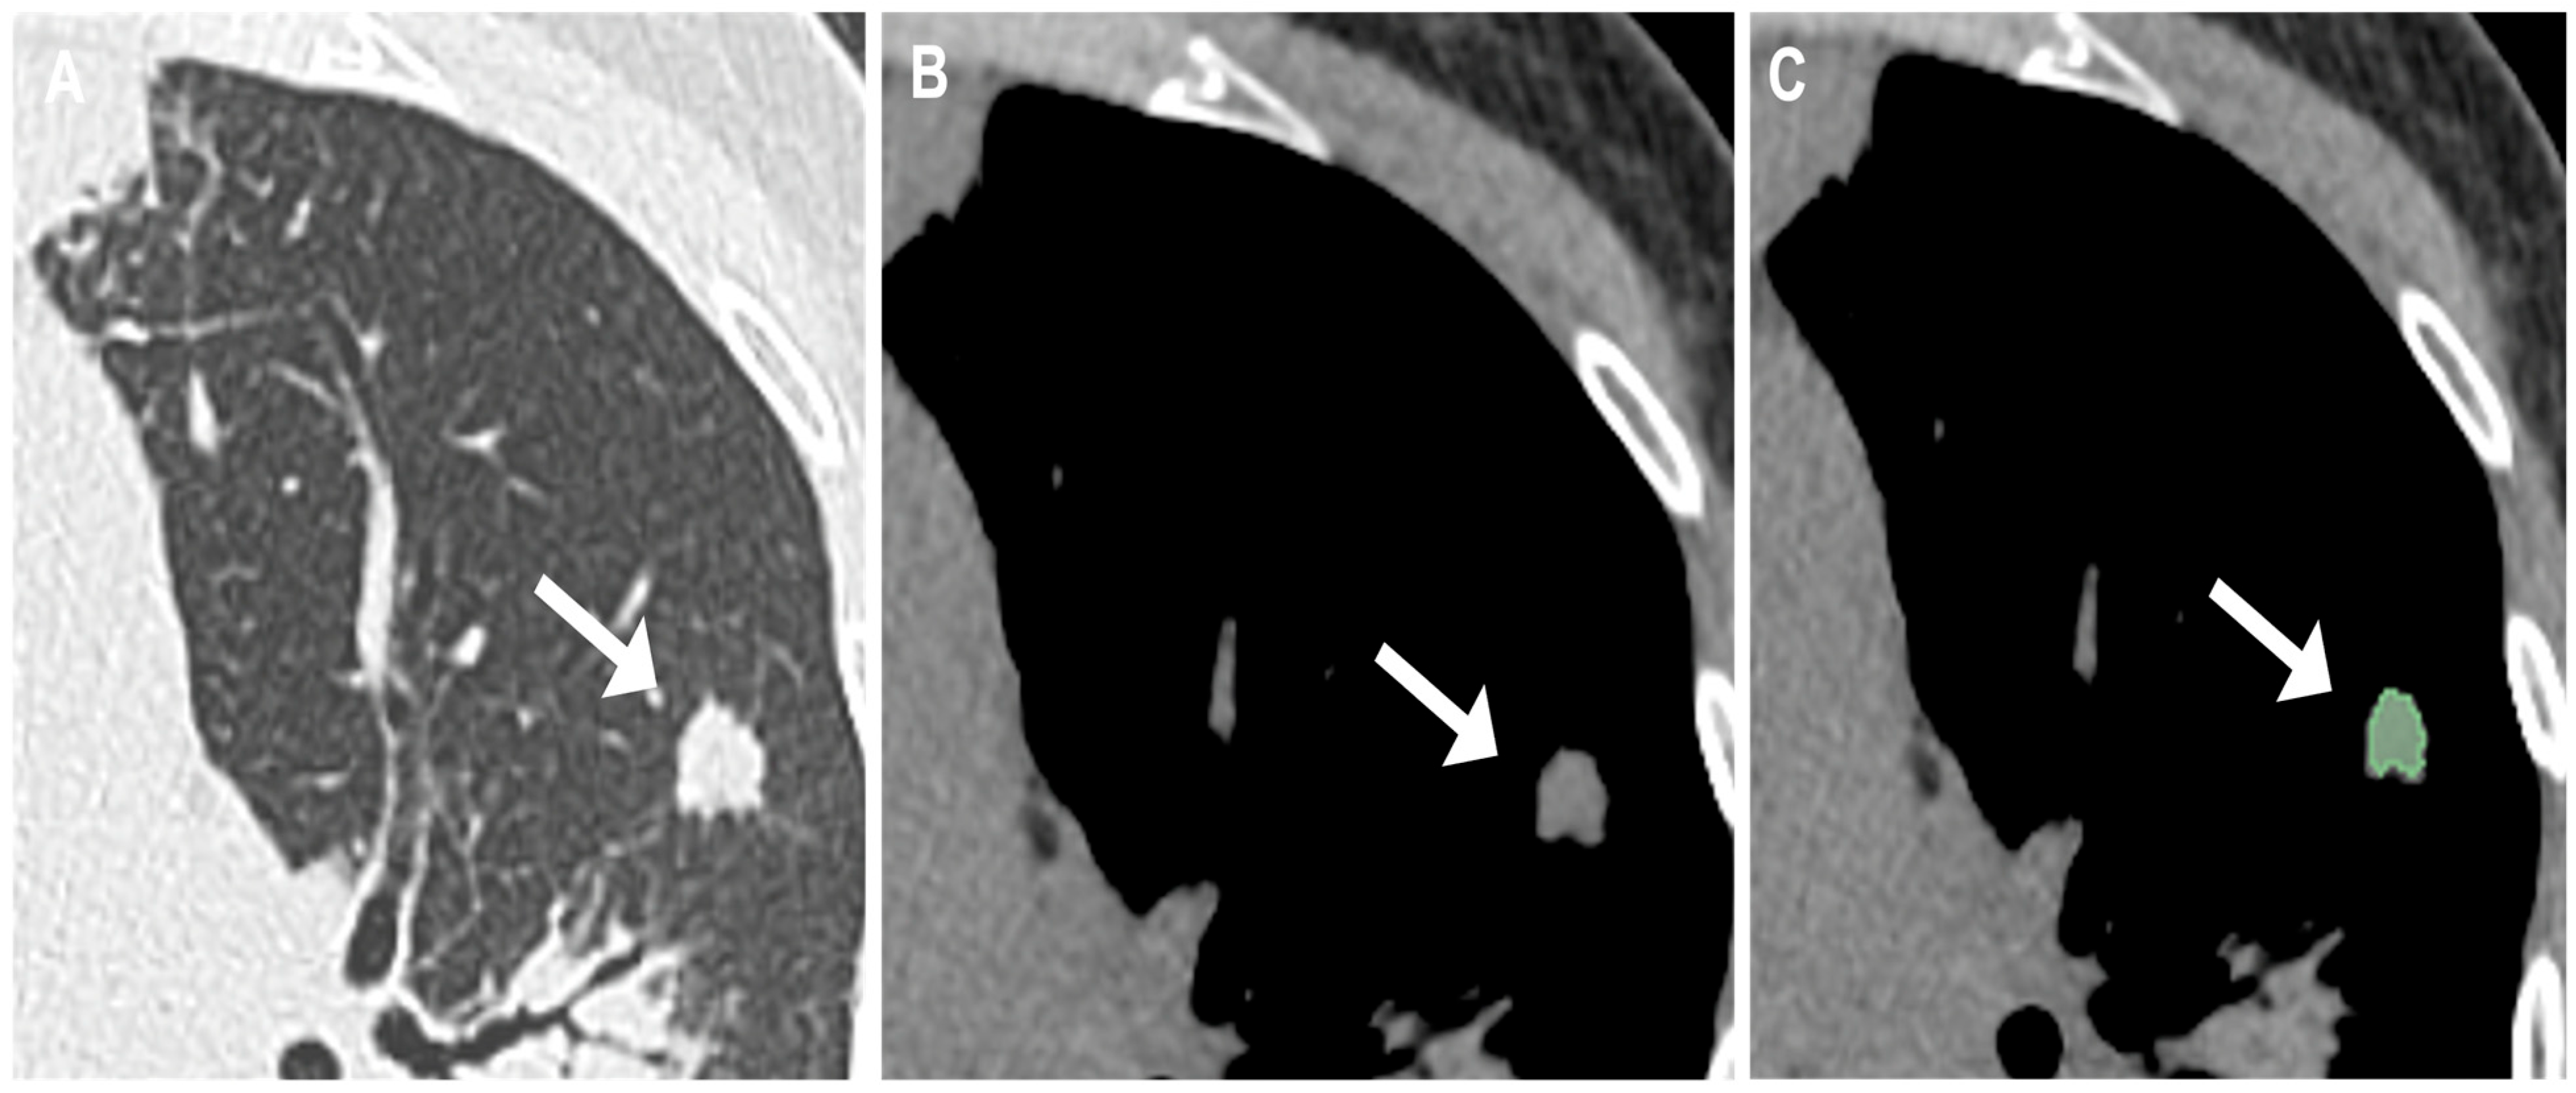

2.3. Evaluation and Segmentation of Chest CT Images